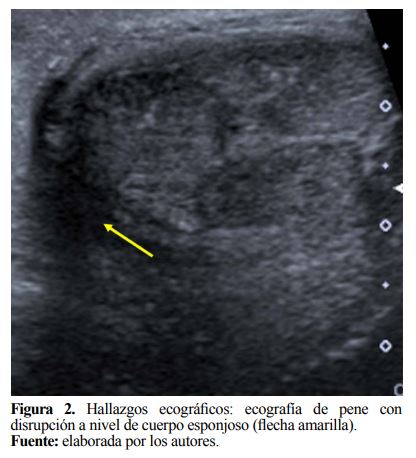

Inicialmente se realizó una ecografía de pene, la cual reportó disrupción en túnica albugínea del cuerpo esponjoso a nivel de la raíz, hematoma que se localizó inferiormente al mismo, con un volumen de 24cc, e imagen sugestiva de disrupción de uretra peneana (Figura 2). Se indicó exploración quirúrgica de pene 6 horas posterior al trauma, se encontró hematoma escrotal de 30cc a nivel de unión peno escrotal (Figura 3a), edema de tejidos blandos de pene y escroto, secundario a fractura de cuerpos cavernosos derecho e izquierdo hacia ventral, con laceración del 40% de la circunferencia, y transección completa de la uretra y cuerpo esponjoso del 100% de la circunferencia (Figura 3b,3c). Se realizó rafia de cuerpos cavernosos con Vycril 3/0, puntos continuos con adecuado control hemostático, seguido de uretroplastia término-terminal de uretra bulbar con Vycril 5/0 libre de tensión sobre sonda Foley siliconada (Figura 3d,3e).

Pavan et al. (12) reportan que el diagnóstico se alcanza en un 90% de los casos solo basado en historia clínica y un adecuado examen físico; sin embargo, el uso de ayudas diagnósticas es útil para precisar de manera exacta el defecto en la túnica albugínea, por ejemplo, Hatzichristodoulou et al. (13) describen el uso de cavernosografía o resonancia magnética; la primera es un procedimiento invasivo con riesgo de aumento de hematomas y de fibrosis al usar radiación ionizante, y la resonancia permite mayor detalle anatómico pero no se realiza de manera rutinaria por su alto costo y poca disponibilidad (14). Dada la extensa equimosis y edema que cursó el paciente se decidió realizar estudio ecográfico, el cual permitió la localización del defecto y así determinar la planificación quirúrgica más conveniente.